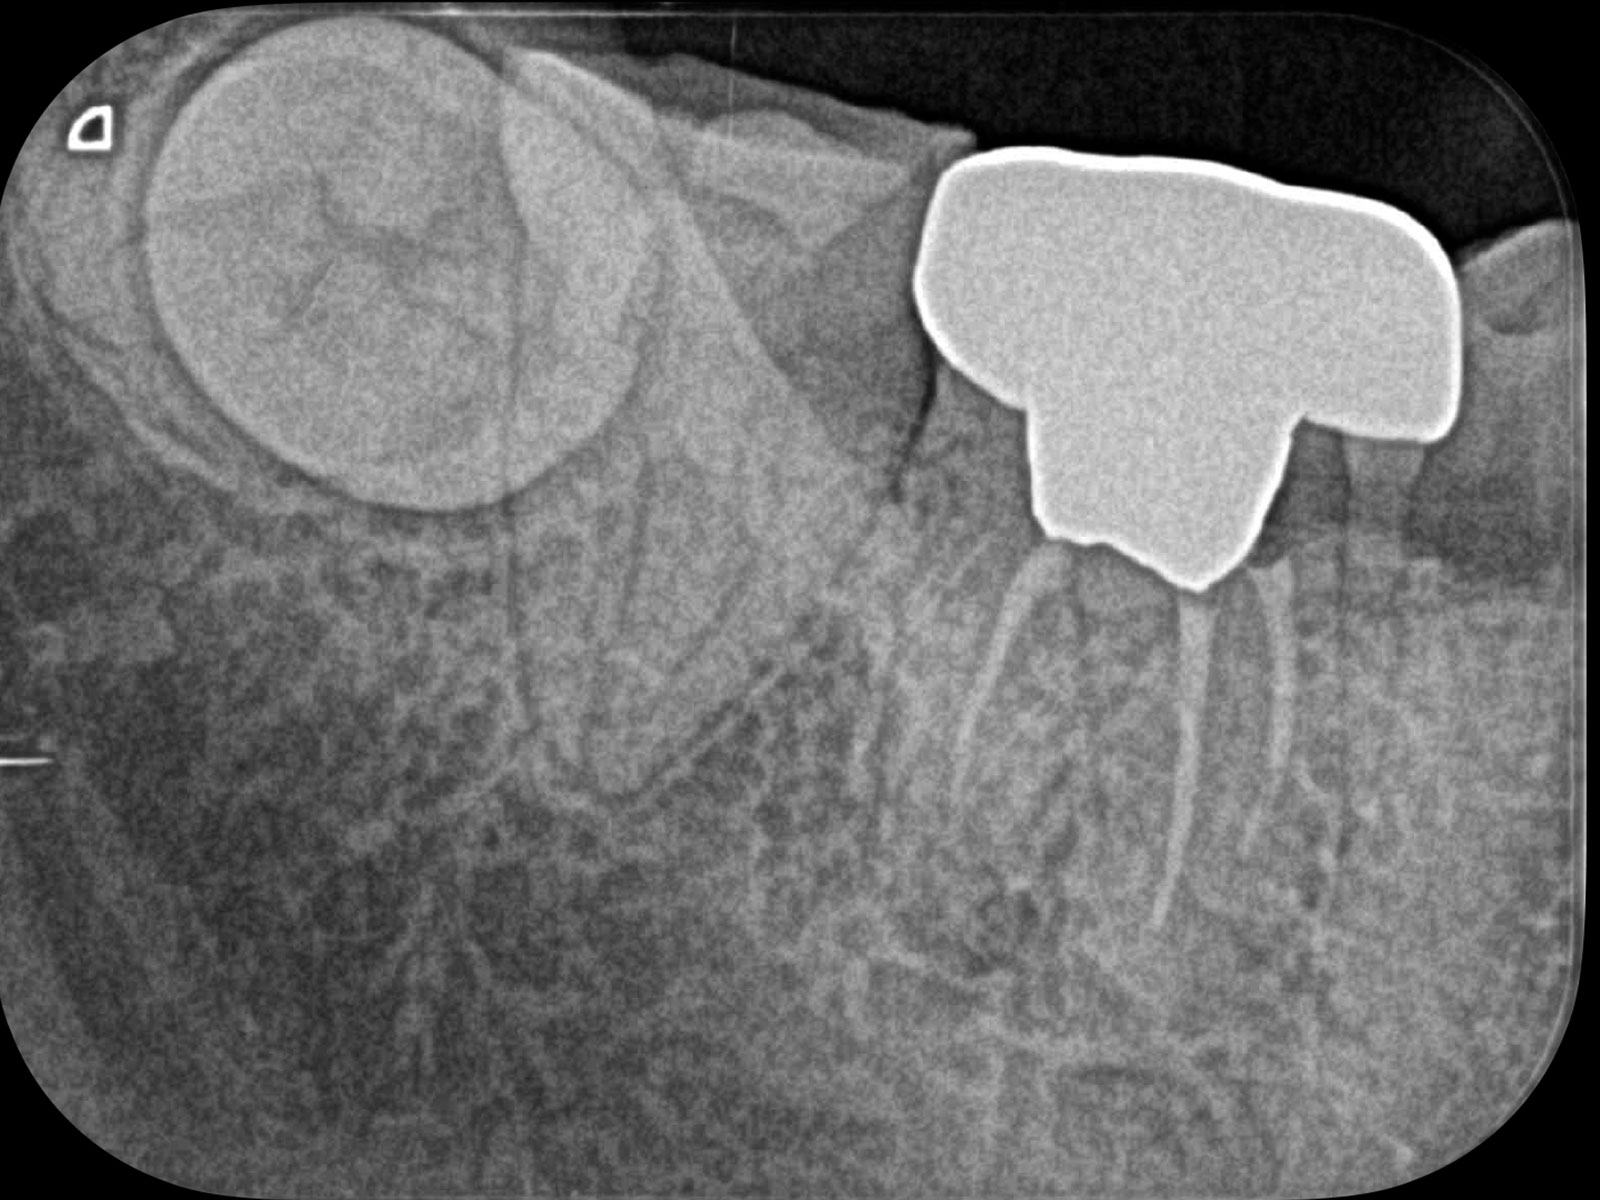

主訴: 噛むと痛い、左で食べれない。他の病院で神経が見つからない。根の先に病気がある。

通常だと手立てがなく、抜歯しかない歯も外科(根尖切除術)で治すことができます。

丸の部分が病巣です。CT画像によって、左の画像(Before)では黒く映っている病巣が右の画像(After)ではなくなっていることが確認できます。レントゲン画像ですと、ここまでクリアに写りませんので、病巣を見落としてしまう可能性があります。